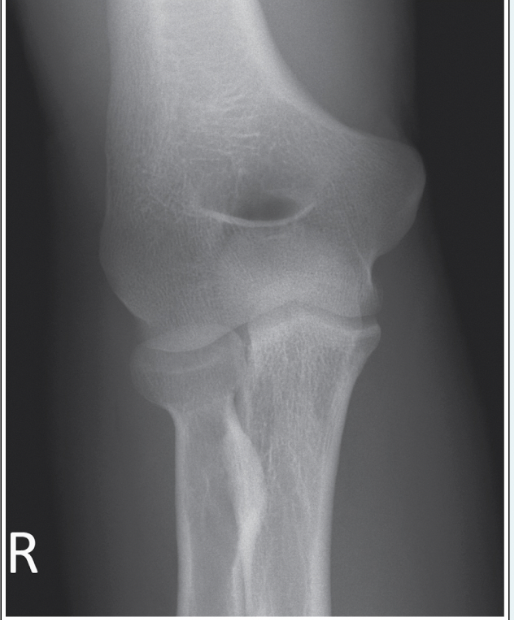

46

What type of fracture is evident? a.Smith’s fracture b.Stress fracture c.Greenstick fracture d.Colles’ fracture

d.Colles’ fracture